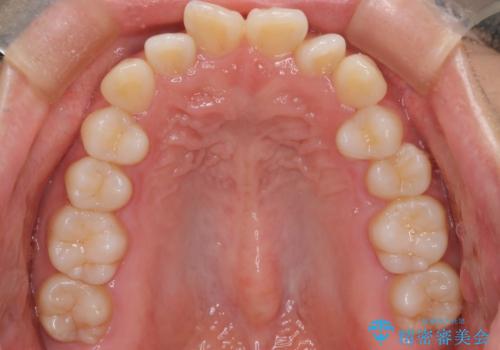

- 「前歯が出ているのが気になる」との主訴で来院されました。診察の結果、上下の前歯が前方に突出し、口元がやや目立つ印象でした。また、歯列の中心線(正中)も上下でずれており、かみ合わせのバランスにも問題がありました。

治療はまず精密スキャンとシミュレーションを行い、TADを使用して奥歯を遠心移動(後方へスライド)させる設計を組み込みました。マウスピースは計画に沿って順次交換し、TADと連結しながらコントロールすることで、歯列全体を無理なく整えていきました。

前歯の傾きが改善され、横顔の印象が大きく変化。上下の正中も一致し、かみ合わせのバランス(臼歯関係)も整いました。目立たず快適に治療ができた点にもご満足いただき、「人に気づかれずにここまで変化できるとは思わなかった」とのお声をいただいています。治療後はリテーナーを用いて、仕上がりをしっかり保っています。